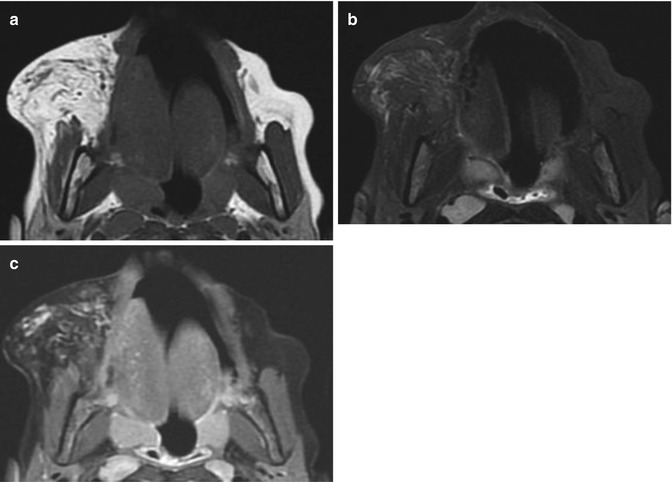

Infantile haemangioma of the cheek in a 7-year-old girl during involution phase. (a) Axial T1-weighted MR image. (b) Axial T2-weighted MR image with fat suppression. (c) Axial T1-weighted MR image after Gadolinium contrast administration with fat suppression. MRI images show a subcutaneous hyperintense mass on T1-weighted image (a), slightly hyperintense on T2-weighted image (b) with minimal enhancement (c). No flow voids are seen